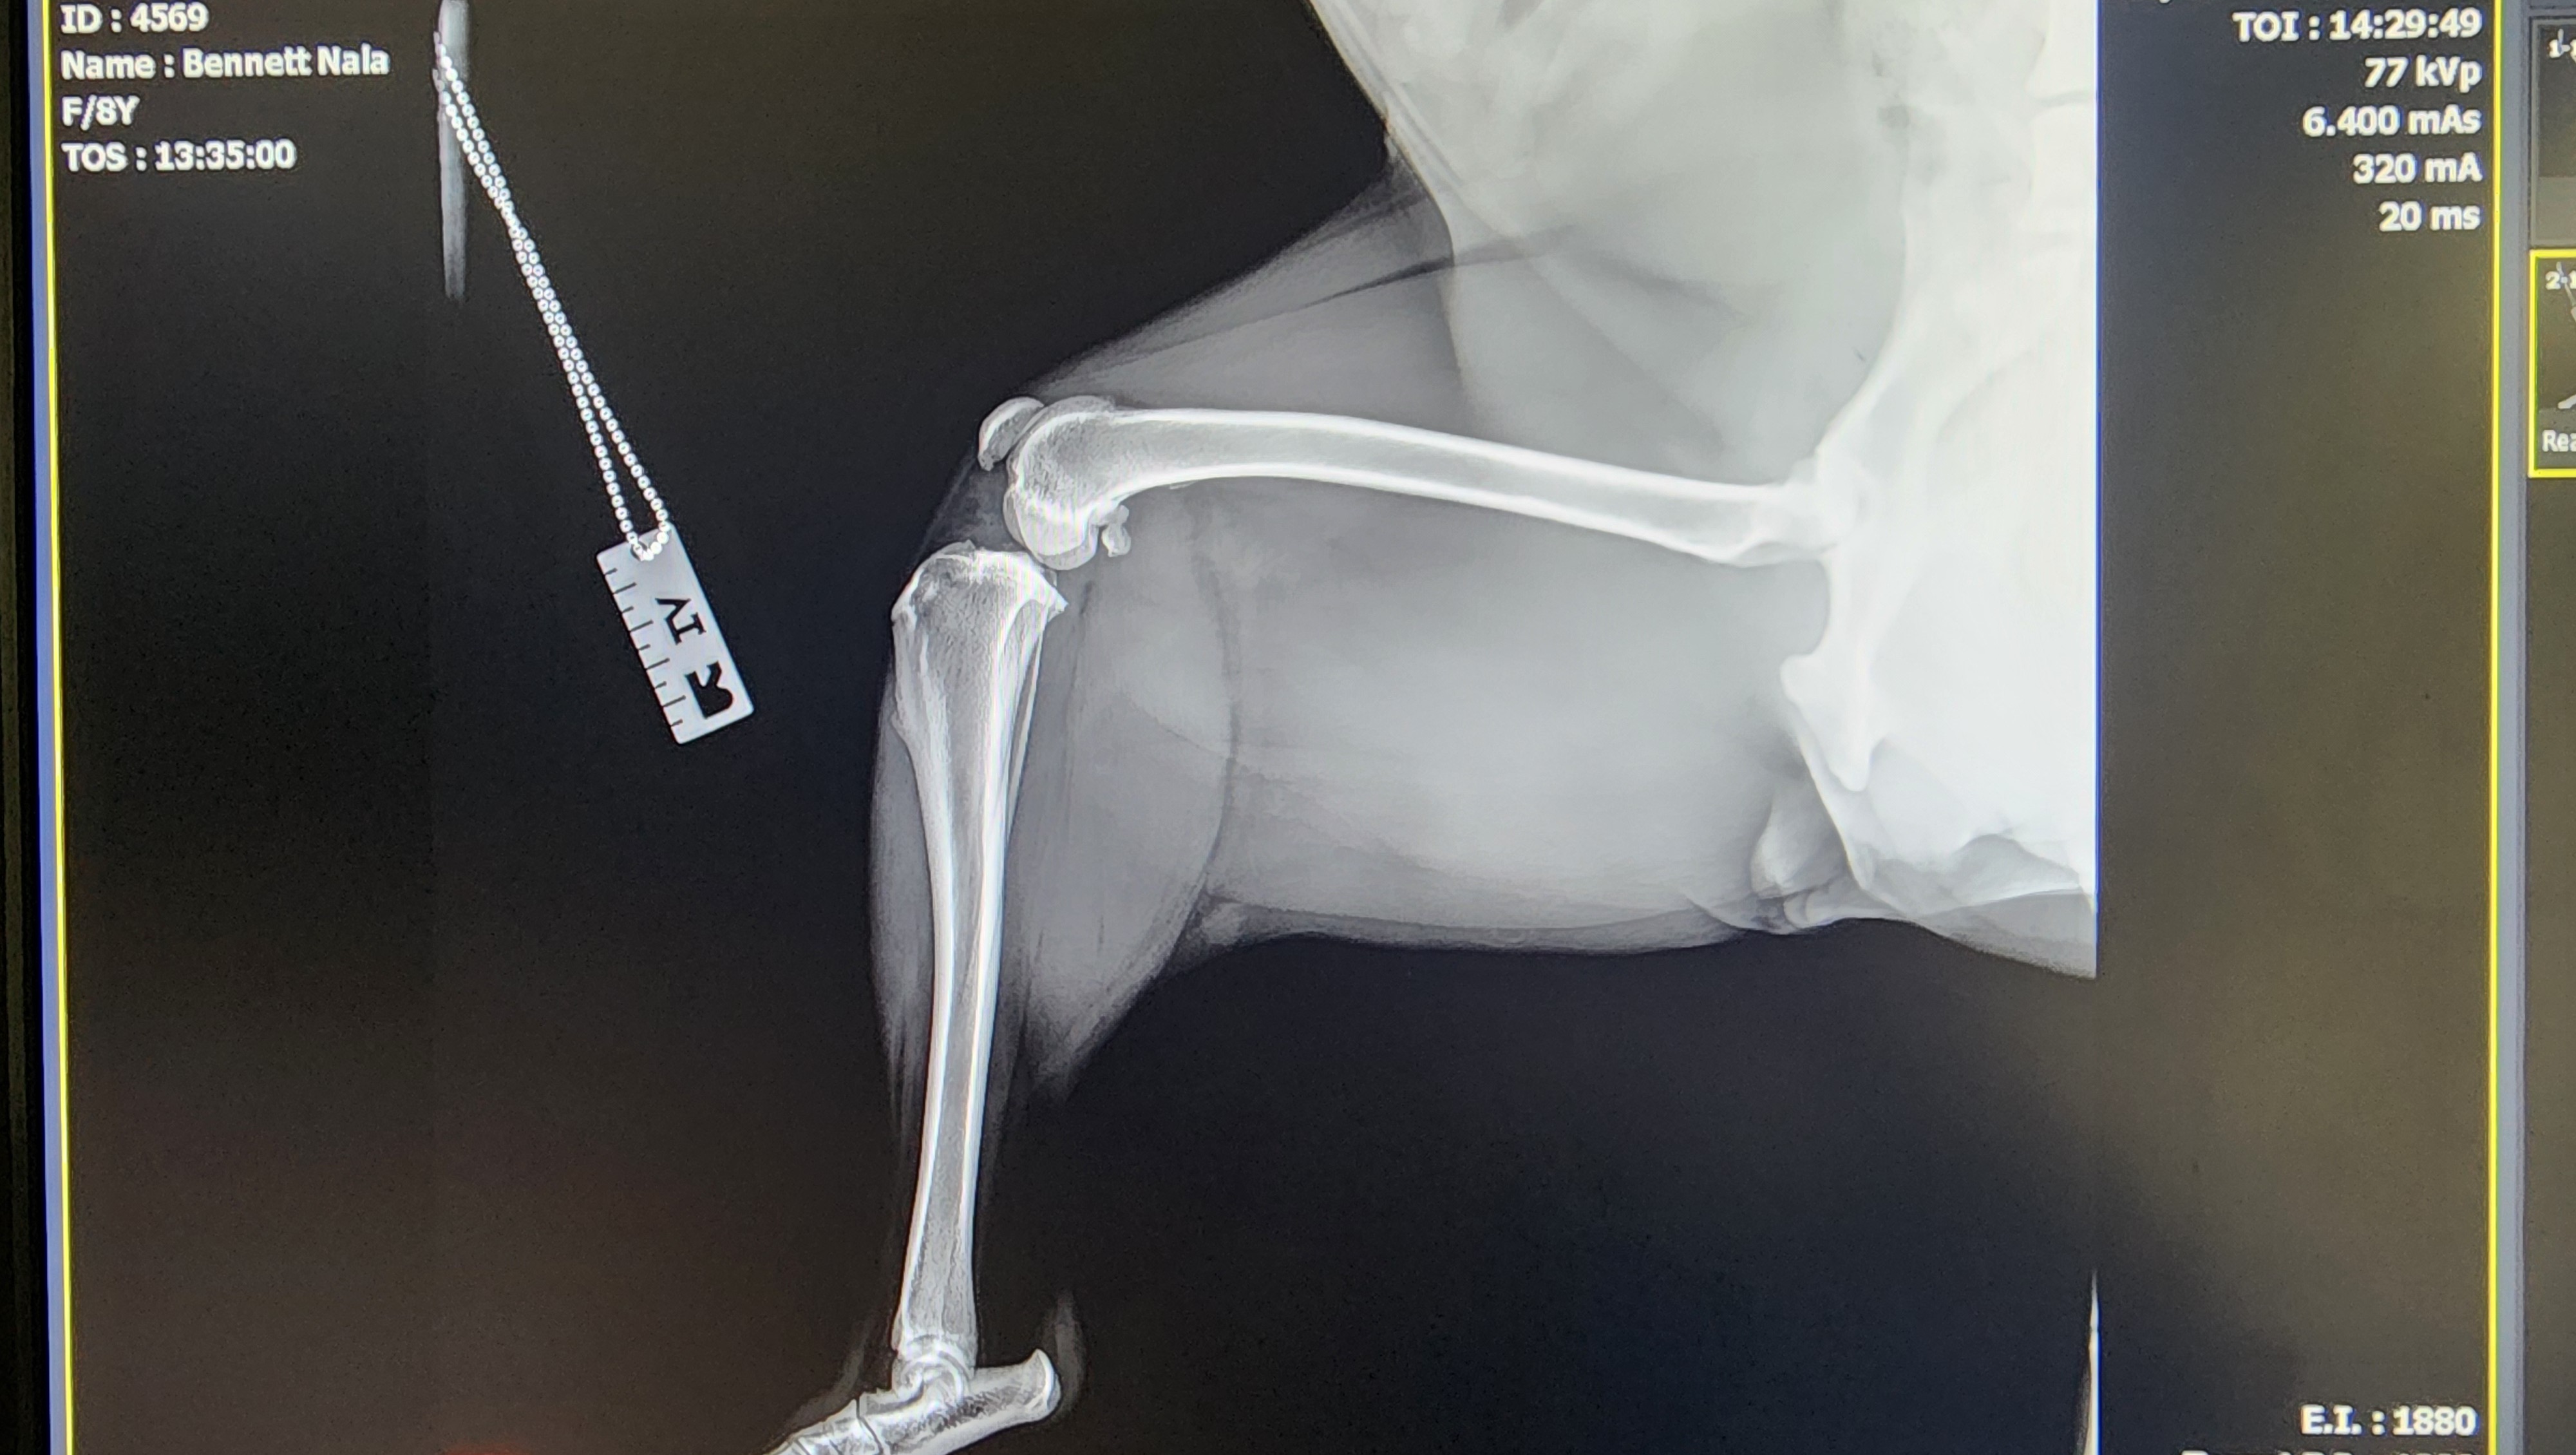

Nala is an 8 year old lab shepherd mix who loves to play soccer and swim. She loves beach runs and the occasional snuggle with mommy. Her best friends are Kovu and Reese with the new family addition of Finn coming to join the pack. She recently was misdiagnosed with hip dysplasia and mild arthritis- she had been limping for about a year. However after receiving sedation and X-rays, a second opinion revealed the diagnosis to be incorrect. She now needs surgery to repair the ligament in her knee allowing her to walk. The current 3 leg hopping is increasing the strain on the remaining ACL in her other knee.